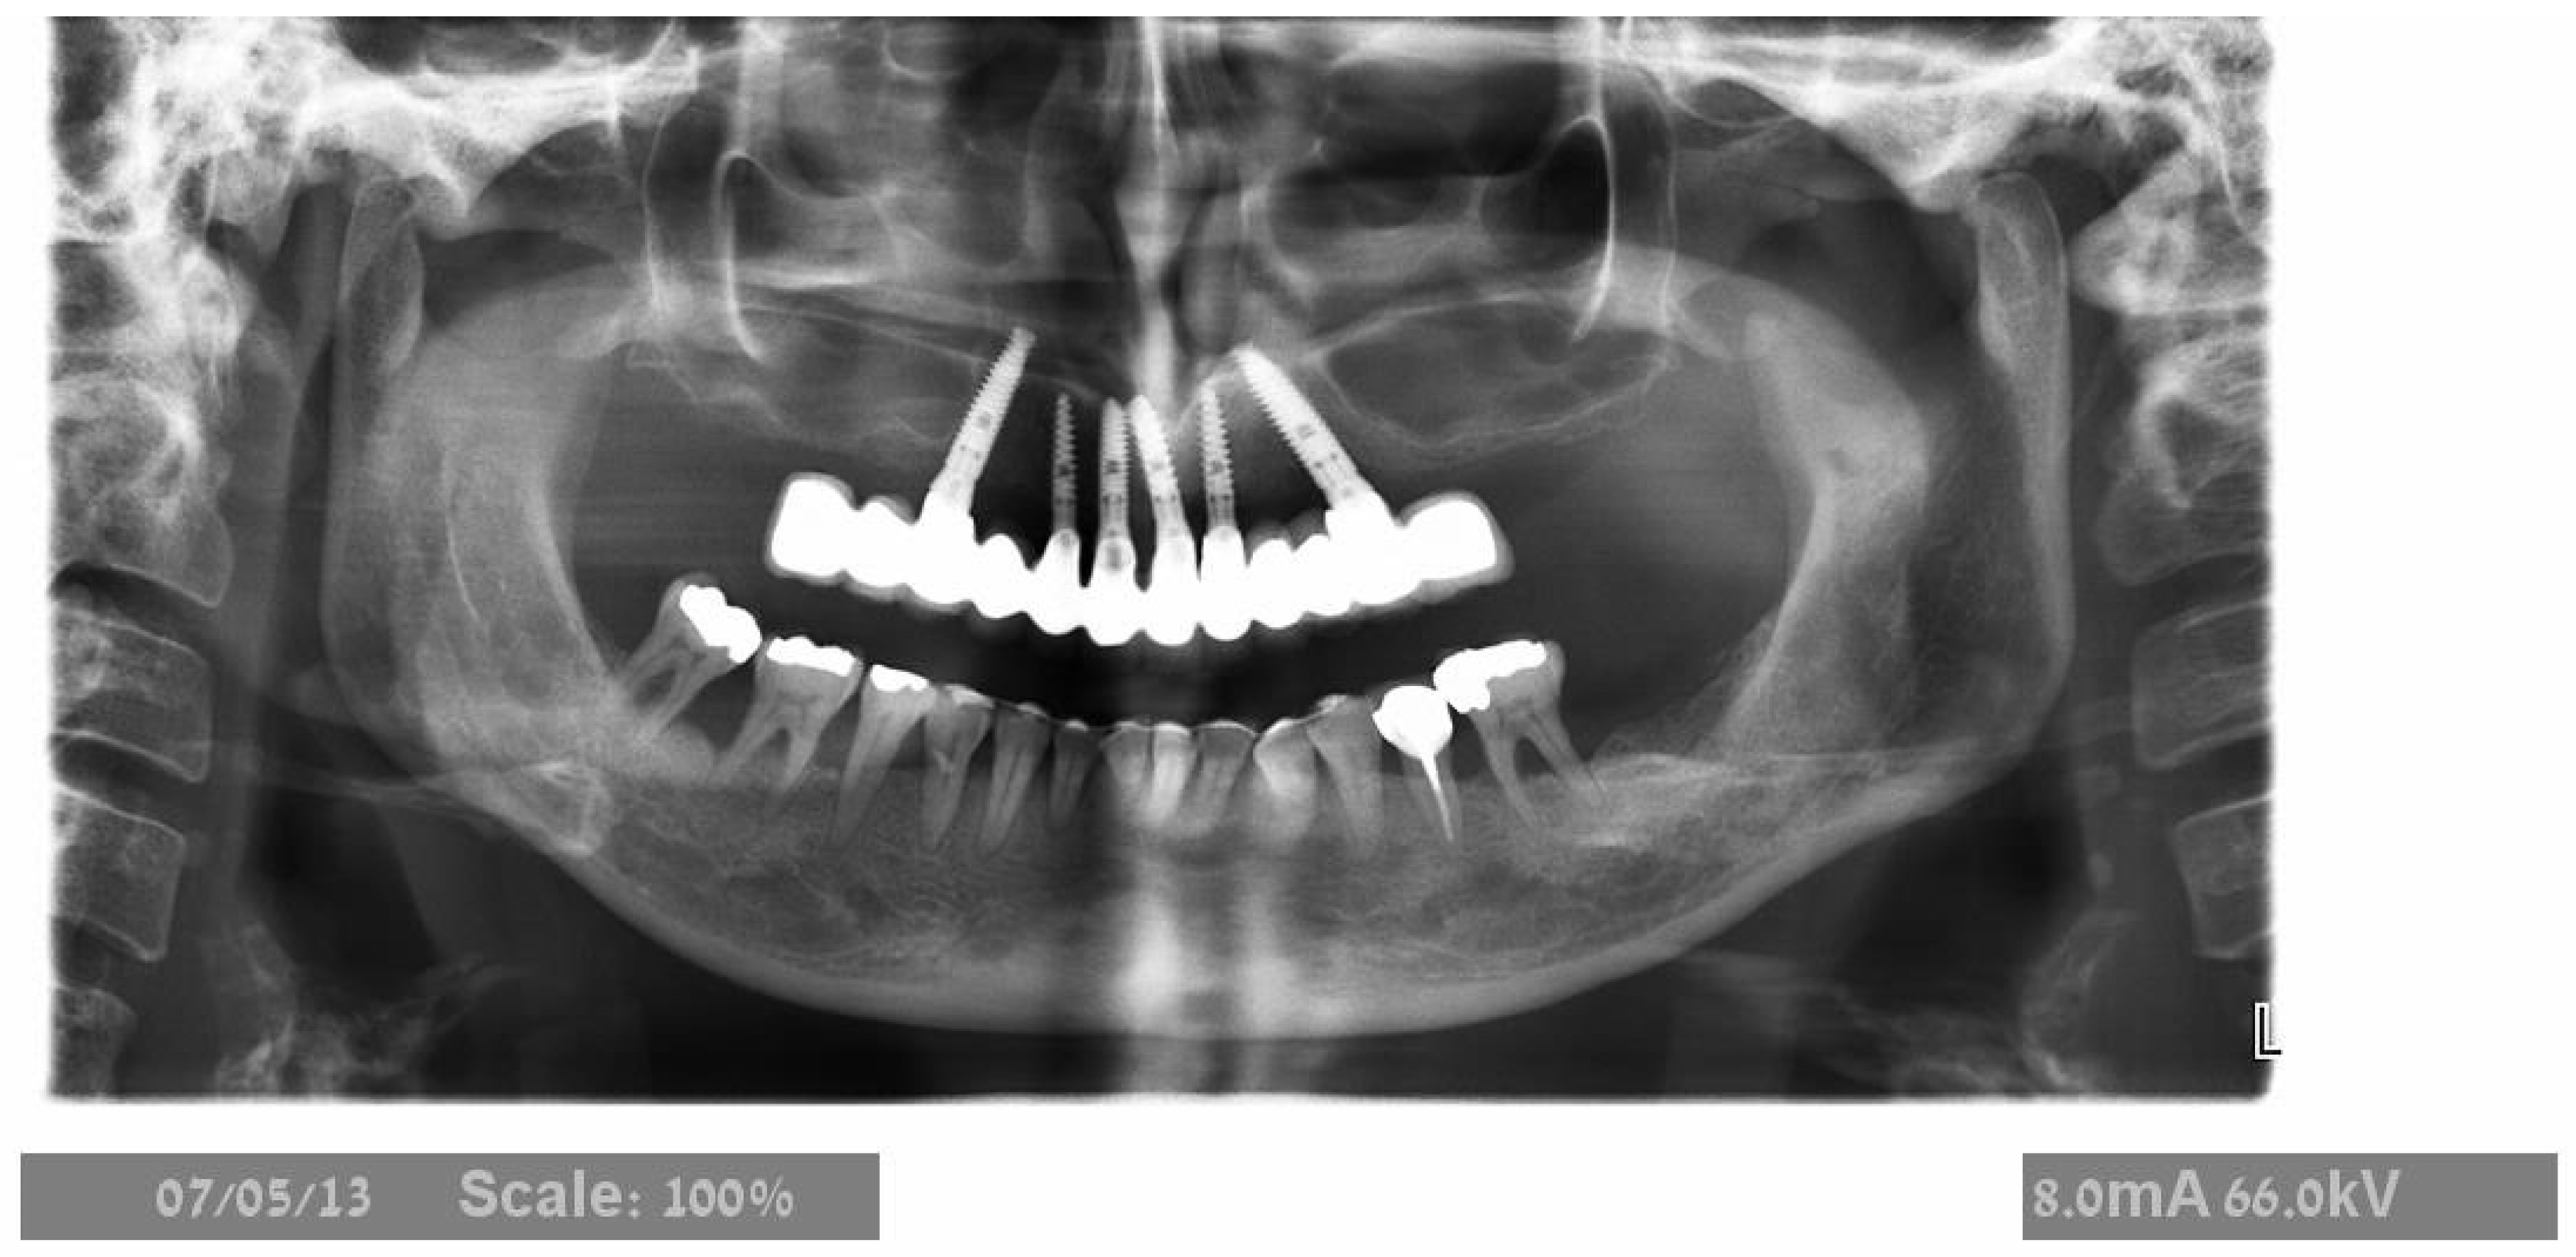

2.2. Surgical Treatment

2.3. Prosthetic Protocol

3.2. Implant Survival and Success Rate